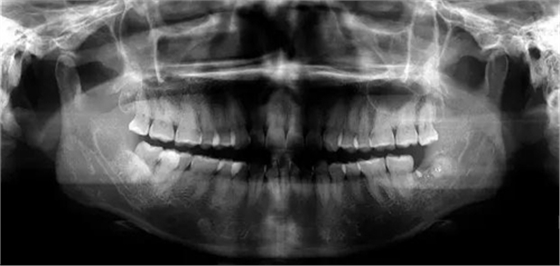

下面看一個(gè)病例,患者,女,30歲,因左下頜智齒嵌塞食物后疼痛,至當(dāng)?shù)匮揽平o予拔除,但術(shù)后1個(gè)半月,患者自覺(jué)拔牙區(qū)一直隱隱疼痛,時(shí)輕時(shí)重,遂來(lái)診。檢查發(fā)現(xiàn),拔牙創(chuàng)口一直未愈合,未見(jiàn)明顯腫脹,拍片發(fā)現(xiàn),拔牙窩內(nèi)顯示高密度斷根影

像,該斷根臨近下頜神經(jīng)管,同時(shí)發(fā)現(xiàn)第二磨牙遠(yuǎn)中有兩塊高密度影像,疑似殘留骨片或牙片,應(yīng)該是引起疼痛的原因,經(jīng)與患者溝通,采納建議,進(jìn)行二次拔牙。